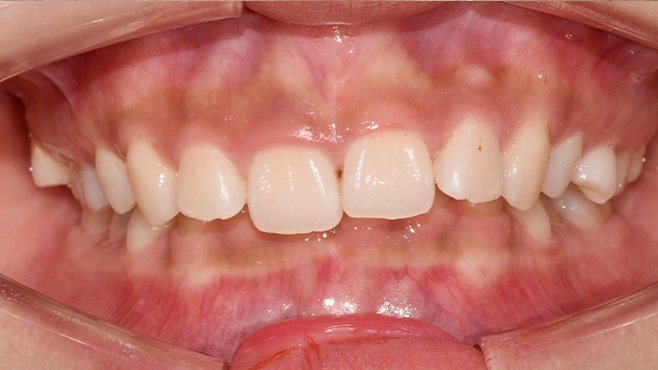

맞는 건 괜찮은데… 충치는 못 참겠습니다|20대 격투기 선수 치과 방문기